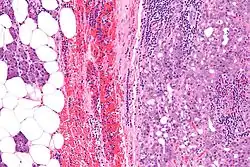

![]() | |

| Micrograph of an acinic cell carcinoma (right of image) and acinar glands (parotid gland - left of image). H&E stain. | |

Histopathologic features

Basophilic, bland cells similar to acinar cells. Growth pattern: solid - acinar cells, microcytic - small cystic spaces mucinous or eosinophilic, papillary-cystic - large cystic lined by epithelium, follicular - similar to thyroid tissue.

These tumors, which resemble serous acinar cells, vary in their behavior from locally aggressive to blatantly malignant.